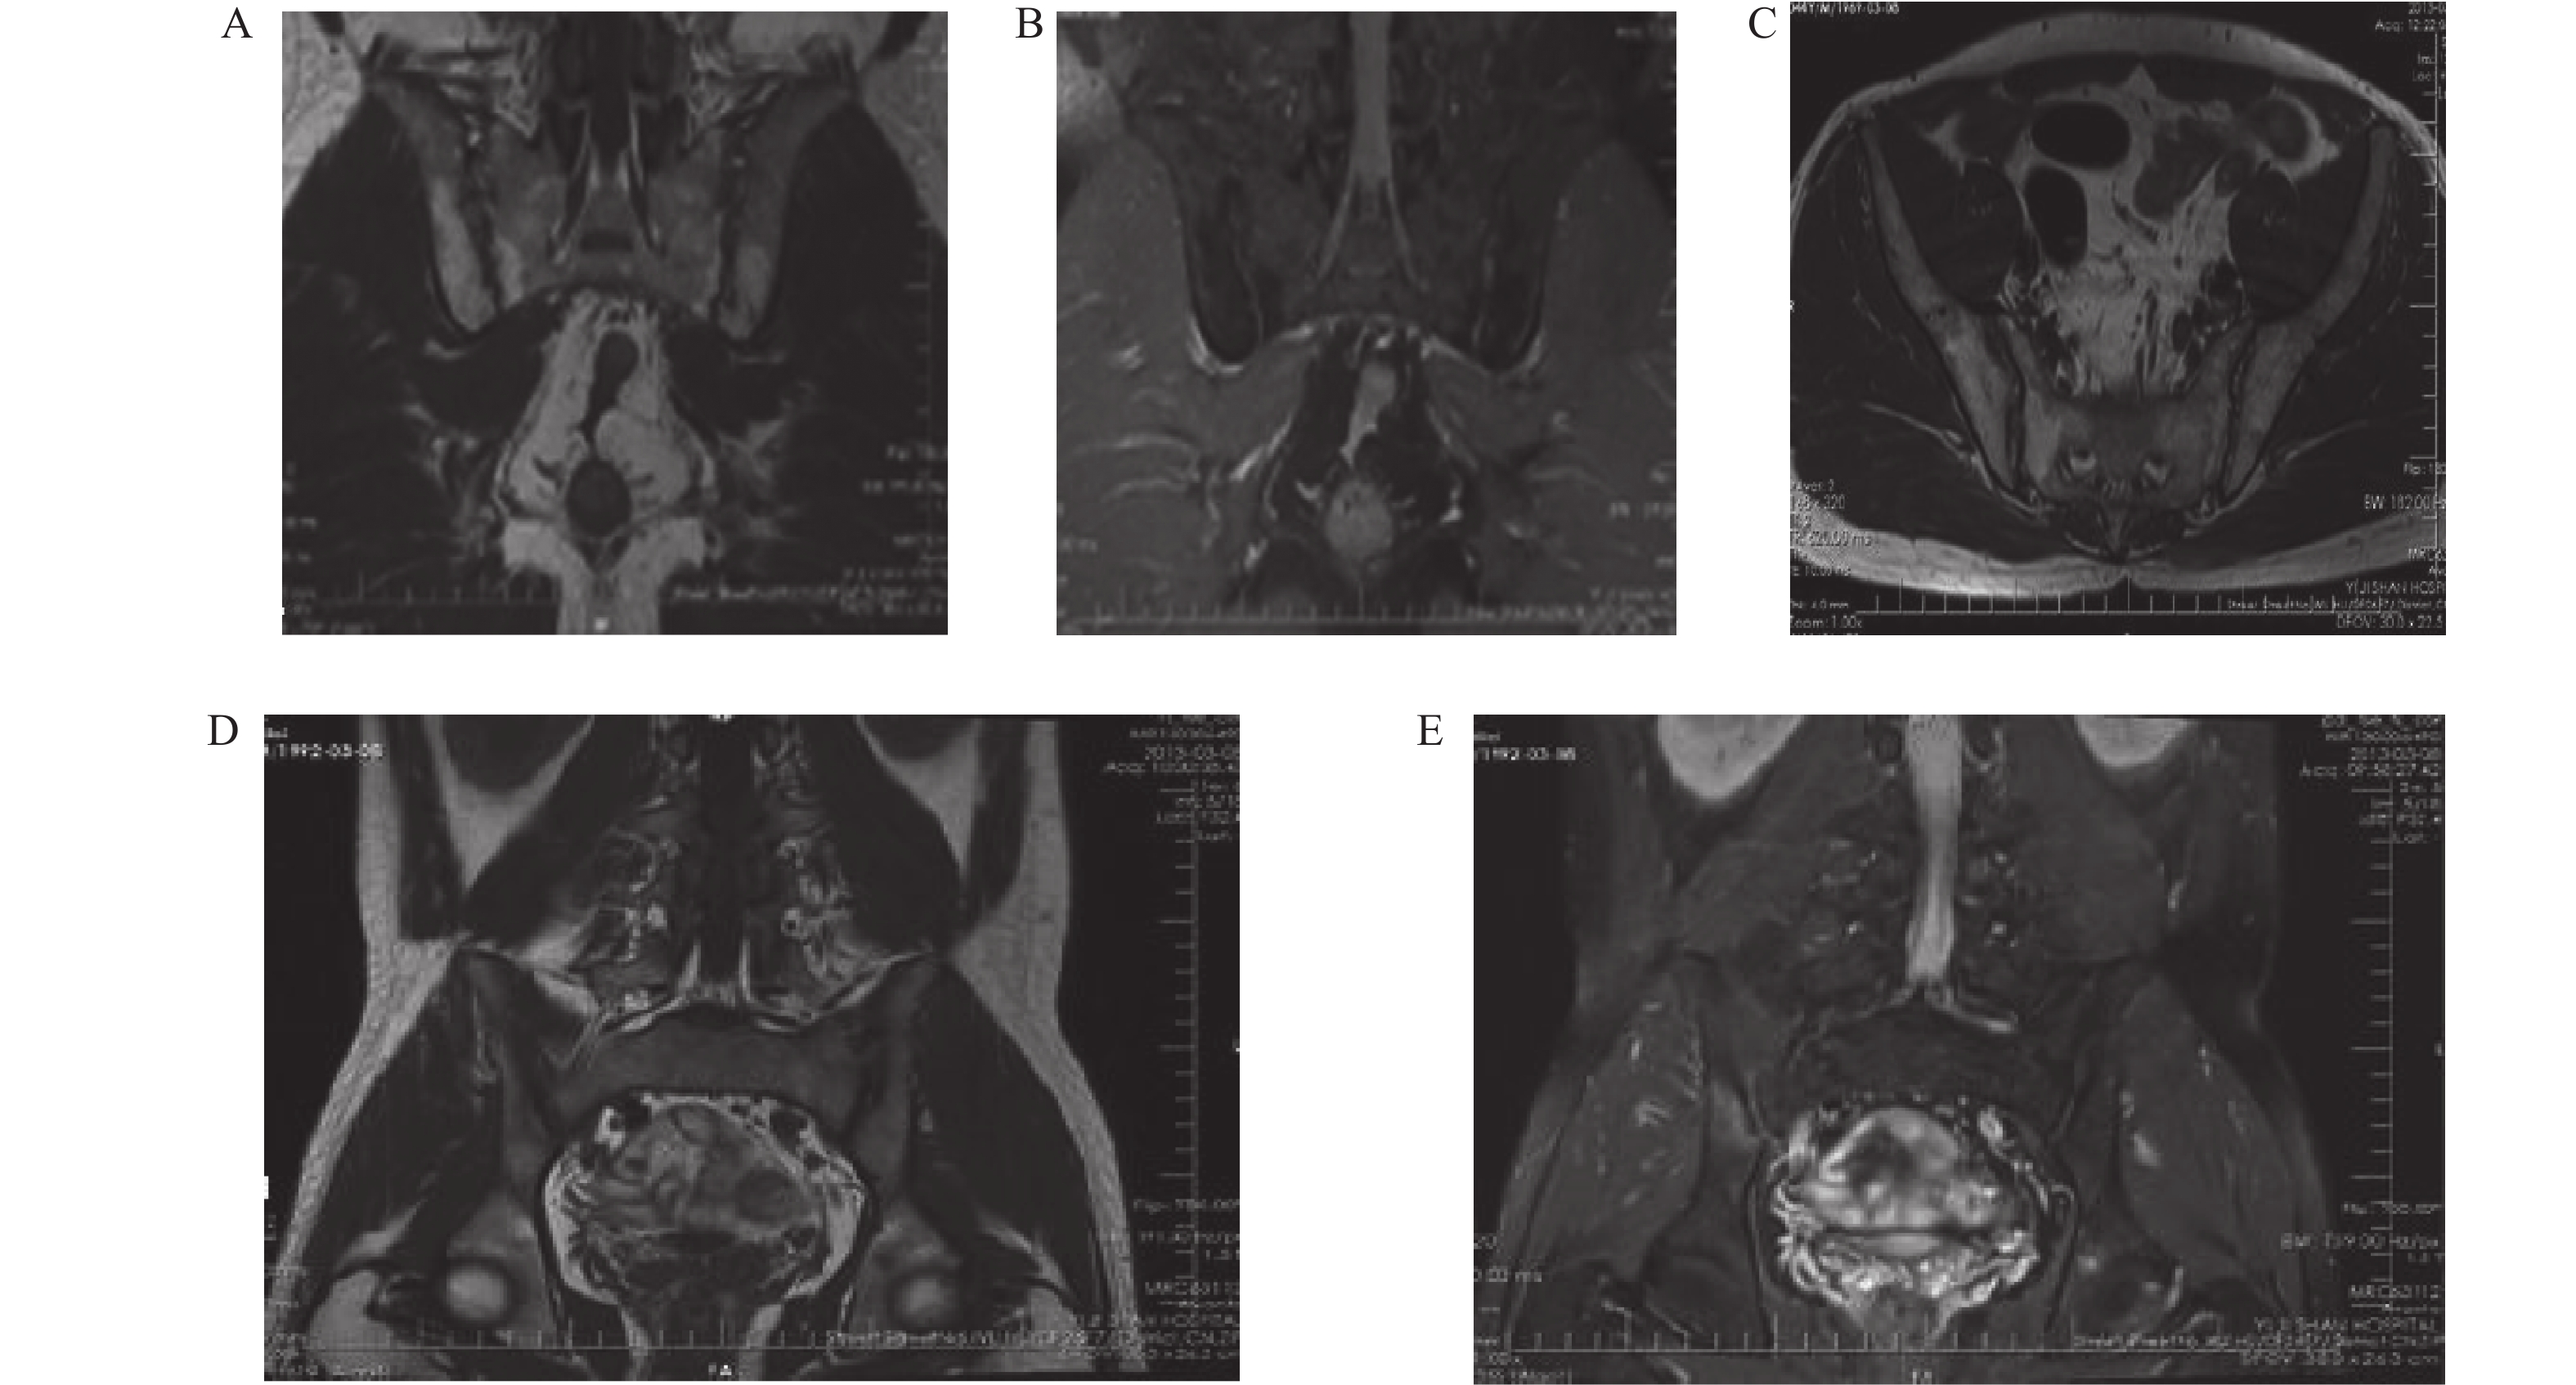

Predictive Value of Combined Detection of IL-10,IFN-γ,PLR,and FIB in Endometrial Lesions

Tianyuan ZHAO, Yanhe CHANG, Xiaoyan NI, Yijun WANG, Xiaoyu LIU, Lijie JIANG

2026, 47(4): 83-89. doi: 10.12259/j.issn.2095-610X.S20260410

Abstract:

Objective  To analyze the predictive value of combined detection of interleukin-10 (IL-10), γ-Interferon (IFN - γ), platelet-to-lymphocyte ratio (PLR), and plasma fibrinogen(FIB) for endometrial lesions.   Method  A total of 306 patients with endometrial lesions admitted to the hospital from April 2022 to January 2024 were included in the study. Based on pathological tissue biopsy, patients were divided into endometrial cancer group (n = 120) and endometrial benign hyperplasia group (n = 186). Sixty-three healthy volunteers from the same period served as control group. The expression levels of IL-10, IFN - γ, PLR, and FIB were measured and compared among the three groups. Receiver operating characteristic (ROC) curve analysis was used to determine the predictive value of IL-10, IFN - γ, PLR, FIB and combined detection for endometrial lesions.   Result  IL-10, PLR, and FIB levels in the endometrial cancer group were higher than those in the benign endometrial proliferation group and control group, while IFN-γ was lower (P < 0.05). IL-10, PLR, and FIB levels in the benign proliferation group were higher than control group, while IFN-γ was lower(P < 0.05). Expression levels of IL-10, IFN-γ, PLR, and FIB showed significant differences among endometrial cancer patients at different International Federation of Gynecology and Obstetrics (FIGO) stages (P < 0.05). Stage IV endometrial cancer patients had higher IL-10, PLR, and FIB levels and lower IFN-γ levels compared to stages I, II, and III (P < 0.05). Serous adenocarcinoma had higher IL-10, PLR, and FIB levels and lower IFN-γ levels compared to endometrioid adenocarcinoma (P < 0.05). Combined detection of IL-10, IFN-γ, PLR, and FIB showed high consistency with pathological diagnosis (Kappa=0.892). Sensitivity was 94.17% (113/120), specificity was 94.38% (235/249), negative predictive value was 97.11% (235/242), and positive predictive value was 88.98% (113/127). The area under the ROC curve (AUC) for combined prediction was 0.904 (95%CI: 0.783~0.957).   Conclusion   Abnormal expression of IL-10, IFN - γ, PLR, and FIB plays an important role in the occurrence and development of endometrial lesions. Combined detection of these four markers has high predictive value for distinguishing different types of endometrial lesions.